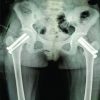

This case report involves a 49-year-old lady who is a biopsy-proven case of triple-negative mammary invasive carcinoma of the left breast and underwent a left mastectomy in 2018. Following which she was on eight cycles of chemotherapy, followed by radiotherapy and hormonal therapy. Two years following mastectomy 1 day while she was on her way for chemotherapy she had a trivial injury to her right hip. She was not able to ambulate post-injury. She came to us with complaints of right hip pain. On examination, she had tenderness over the Scarpa’s triangle and painful hip movements. Endocrinology workup was done which showed reduced serum calcium and elevated serum phosphorous and alkaline phosphatase levels. Radiographs revealed an undisplaced subcapital fracture of the right femoral neck (Fig. 1). Magnetic resonance imaging (MRI) of the spine showed heterointense lesions involving the entire spine in T1/T2 and STIR images (Fig. 2a). MRI also revealed osteolytic lesions in the contralateral neck of femur (Fig. 2b). Positron Emission Tomography scan was suggestive of extensive skeletal metastasis involving the entire axial skeletal system, bilateral humerus, ribs, bilateral scapula, and bilateral proximal femur (Fig. 3a and b). After a thorough review of the literature and assessing all possible options of intervention, the patient underwent right hip bipolar uncemented hemiarthroplasty following an anesthetic workup (Fig. 4). The femoral head was sent for histopathological examination. Intraoperative biopsy revealed fragments of bony trabeculae enclosing suppressed marrow elements and fat infiltrated by a tumor composed of singled-out cells which are eosinophilic in nature with peripherally pushed hyperchromatic nucleus showing atypia and mitosis (Fig. 5). Thus confirming the metastatic spread to the femoral head. Postoperatively, patient was advised strict bed rest and was not allowed to weight bear post-procedure. The patient was regularly followed up 2 weeks, 4 weeks, and 6 weeks post-procedure. Forty-five days post-procedure, subsequently patient had another episode of trivial injury to her left hip. She was worked up again through the same protocols and she diagnosed with a transcervical undisplaced left neck of femur fracture (Fig. 6). Patient again underwent bipolar uncemented hemiarthroplasty in the contralateral hip (Fig. 7). The patient was followed up in regular intervals. There was no periprosthetic joint infection, loosening of femoral stem, periprosthetic fractures or dislocation in the post-operative period. At 3 months, follow-up functional and radiological outcomes were assessed and were satisfactory. However, patient had another trivial injury to her left humerus which revealed undisplaced fracture of humeral shaft (Fig. 8). We did not want to operate her due to increased risk of perioperative cardiac and neurological worsening of patient. Henceforth, she was managed conservatively with custom-made thermoplastic splint. She was again followed up serially and the fracture healed well without any functional compromise (Fig. 9).